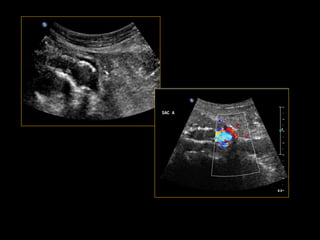

Aspect normal: Doppler

Aspect normal

Contraste mode dédié